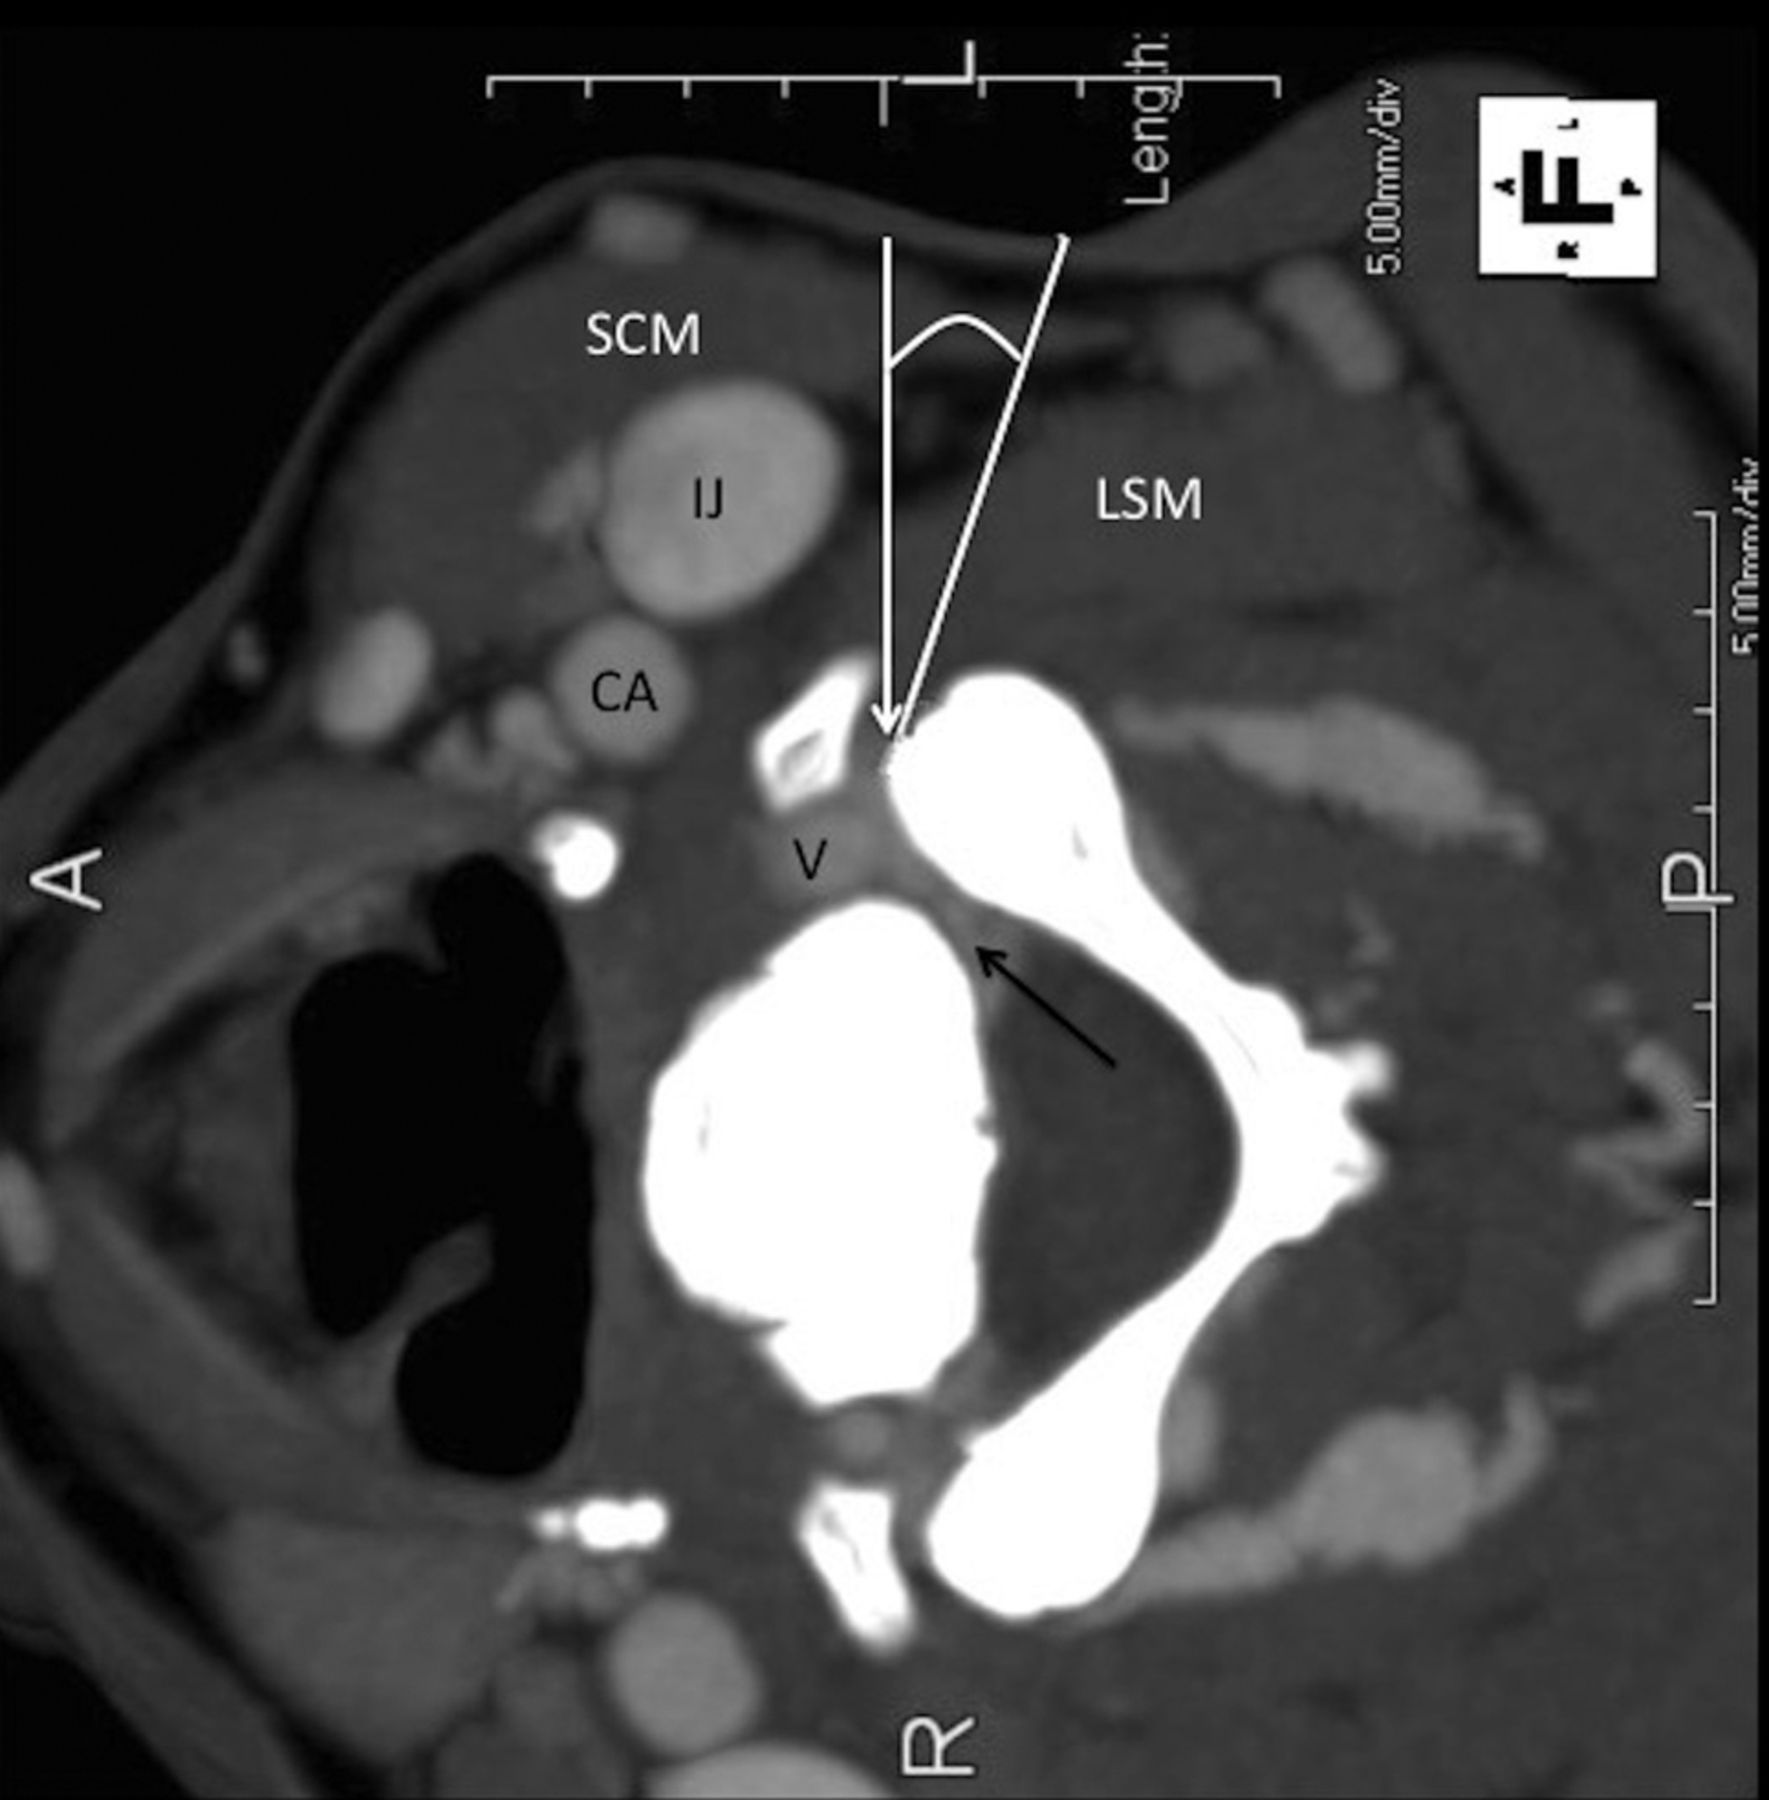

Although commonly performed with fluoroscopic guidance, CT guidance offers many potential advantages.4,5 As seen in Fig 1, direct visualization of soft-tissue planes, vital organs and glands, and neural and vascular structures and precise anatomic localization with millimeter accuracy are all features that make CT attractive as a guidance technique. Lack of real-time vascular contrast imaging is a potential limiting feature.6,7

Lateral decubitus position: anatomy and targeting. CT scan with contrast. The white line indicates the deviation from the perpendicular approach; the black arrow, the perineural venous plexus; the white arrow, the target at the anterior margin of the facet. SCM indicates the sternocleidomastoid muscle; IJ, internal jugular vein; CA, carotid artery; V, vertebral artery; LSM, levator scapulae muscle.